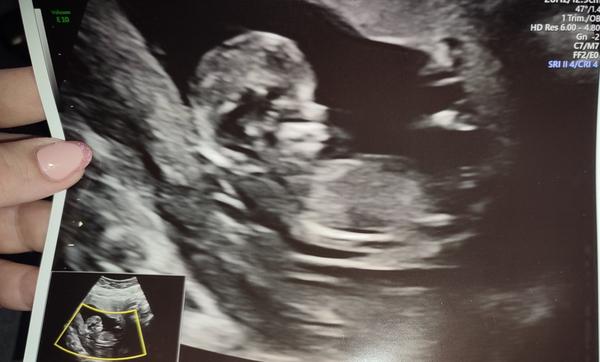

@majina jezisinkyyy 🥰🥰🥰tak vidíš 🥰 gratuluju 🥰

Jen tedy odpovídá 12+6, takže k vám vlastně už nepatříme, termín porodu 30.6. ale my bychom tu rádi zůstali 🙏😂